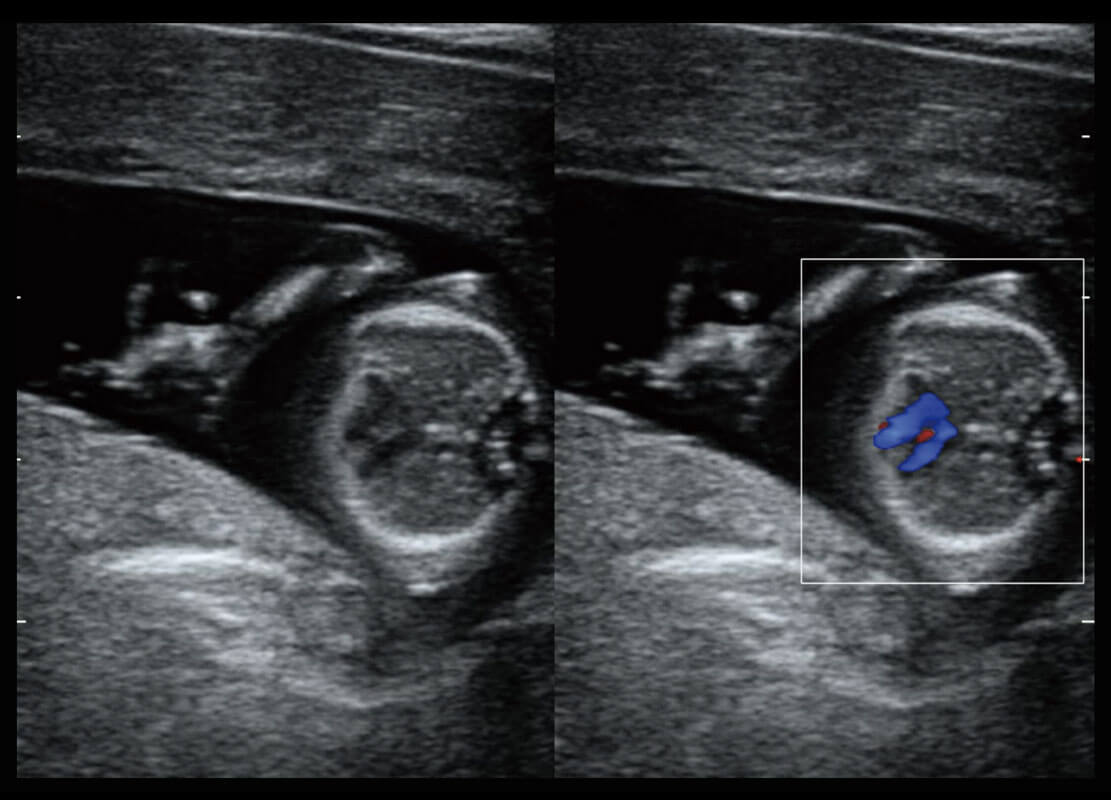

早孕筛查

P60在胎儿早孕期超声筛查中为您带来优异的图像质量。

• 早孕-胎心

• 高分辨率容积成像-早孕胎儿

• 胎儿体循环

• 光影成像-孕囊